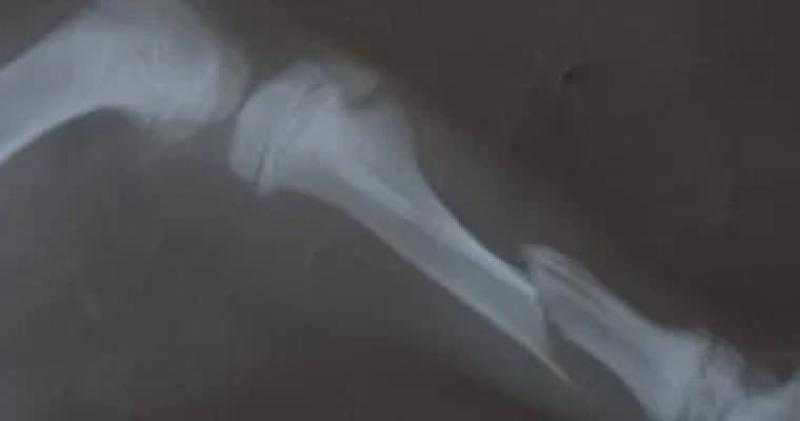

جراحة ناجحة لتثبيت عظام ساق كلب عمره 3 شهور تعرض لحادث سيارة بالغربية